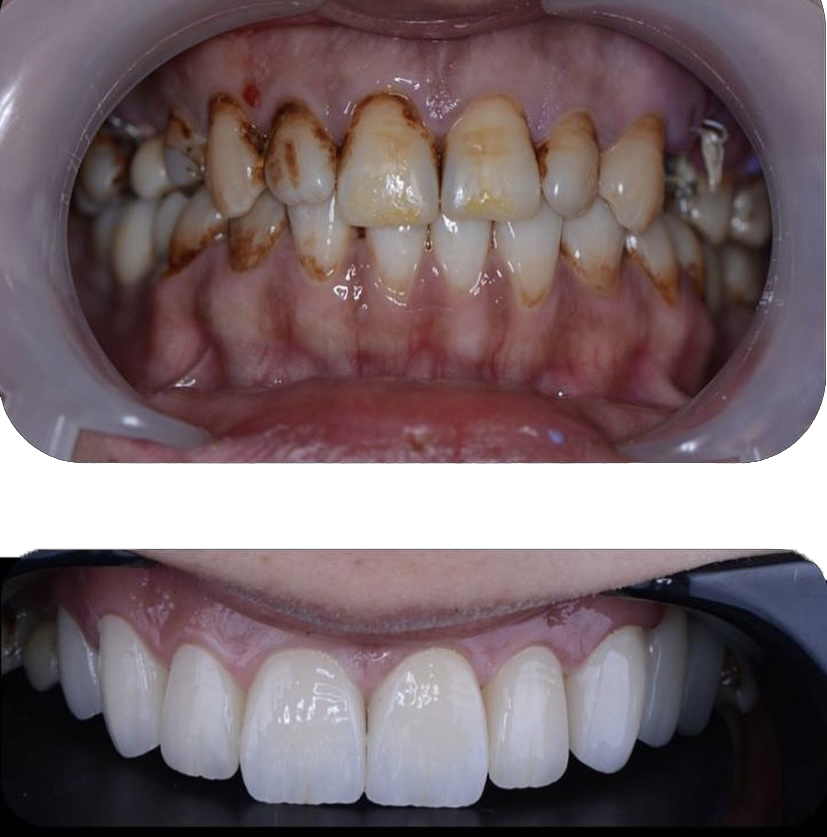

Öncesi̇-Sonrası Resi̇mler

Galeri Öncesi̇-Sonrası Resi̇mler